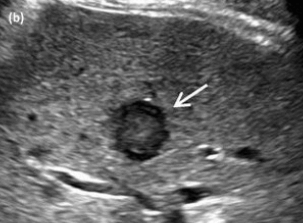

US finding

- 동일한 크기의 다발성 종괴가 나타난다.

- 고에코의 다발성 종괴: 대장암이 많으나 위암도 비교적 흔하다.

- 저에코의 다발성 종괴: 유방암, 폐암등에서 나타난다.

- 석회화나 내부 낭성 변성은 전이성 간종양을 시사하는 소견이다.

- bull's eys sign (종양 변연에 중심부가 고에코이고 경계부가 저에코인 두꺼운 띠가 보인다)

- cluster sign (종양이 융합하여 분엽모양을 이루어 마치 포도송이 모양을 나타낸다)